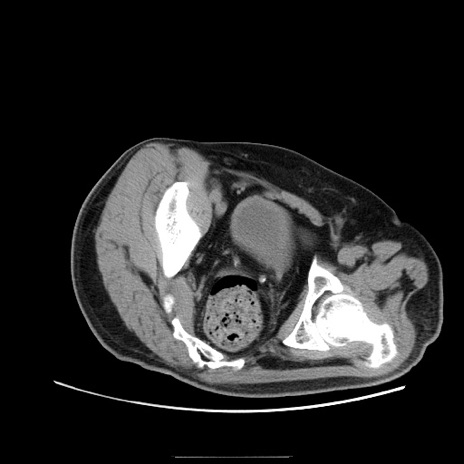

冠状断像

【症例】50歳代男性

【主訴】腹痛

【現病歴】AVMからの被殻出血のため回復期リハ病棟入院中。 本日午後3時頃急に下腹部痛が出現した。

【既往歴】AVM、被殻出血、虫垂炎、高血圧

【身体所見】意識晴明、左半身不全麻痺、会話の理解は良好、36.5°C、腹部:膨隆、全体に板状硬、下腹部正中に圧痛点あり、反跳痛-、筋性防御不明、右下腹部にope scar

【データ】WBC 9400、CRP 0.06